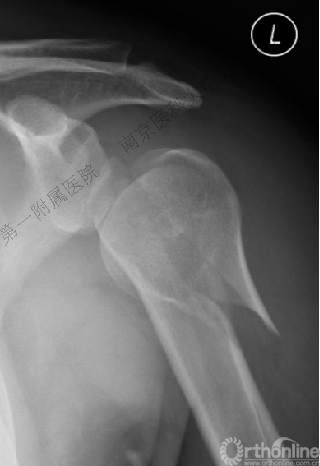

男性,48岁,坠落伤致左肩关节肿痛、活动受限1天。

病例1与病例2是同一类损伤吗?

病例2

VS

病例3

Ⅱ型: +肱骨颈骨折+小结节骨折(病例3)。

Ⅲ型: +肱骨颈骨折+小结节骨折+大结节骨折(病例2),以骨折线向肱骨近端外侧壁延伸为另一特征。